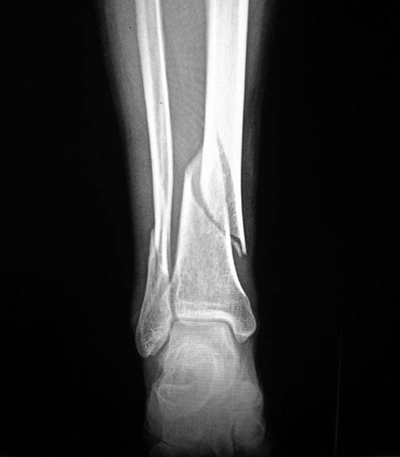

骨折圖片